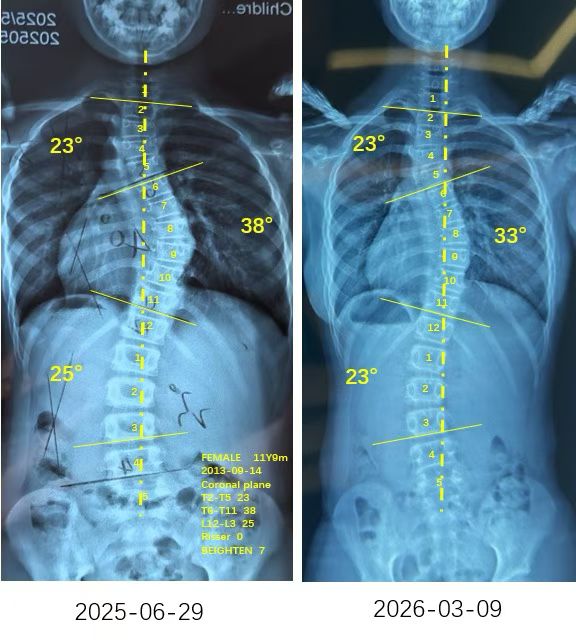

来自家长对衷德的评价(小玉妈妈)

衷德脊柱,我们只关注侧弯保守治疗~

Zhongde Spine, bending no breaking ~